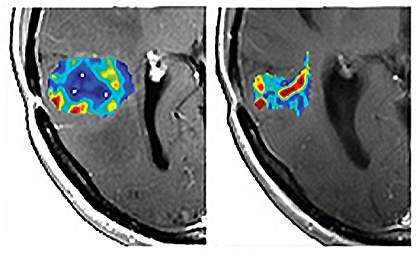

Taking advantage of a previously overlooked feature of MRI scans, the scientists developed and tested a new way of analyzing MRI data, which they termed vessel architectural imaging (VAI). VAI involves a single MRI exam that takes less than 2 minutes and, in most cases, can safely be repeated many times.

To assess the clinical relevance of VAI, the researchers examined MRI images from 30 people with recurrent glioblastomas — fast-growing brain tumors. The patients had been treated in a clinical trial with cediranib, an anti-angiogenesis drug.

Based on VAI analysis, the team identified 10 people who responded to the drug, as evidenced by features such as better microcirculation and structure of the tumor vessels. These responses might lead to better delivery of therapies and thus better outcomes. The researchers also identified 12 people who didn’t respond to the drug based on the MRI data.